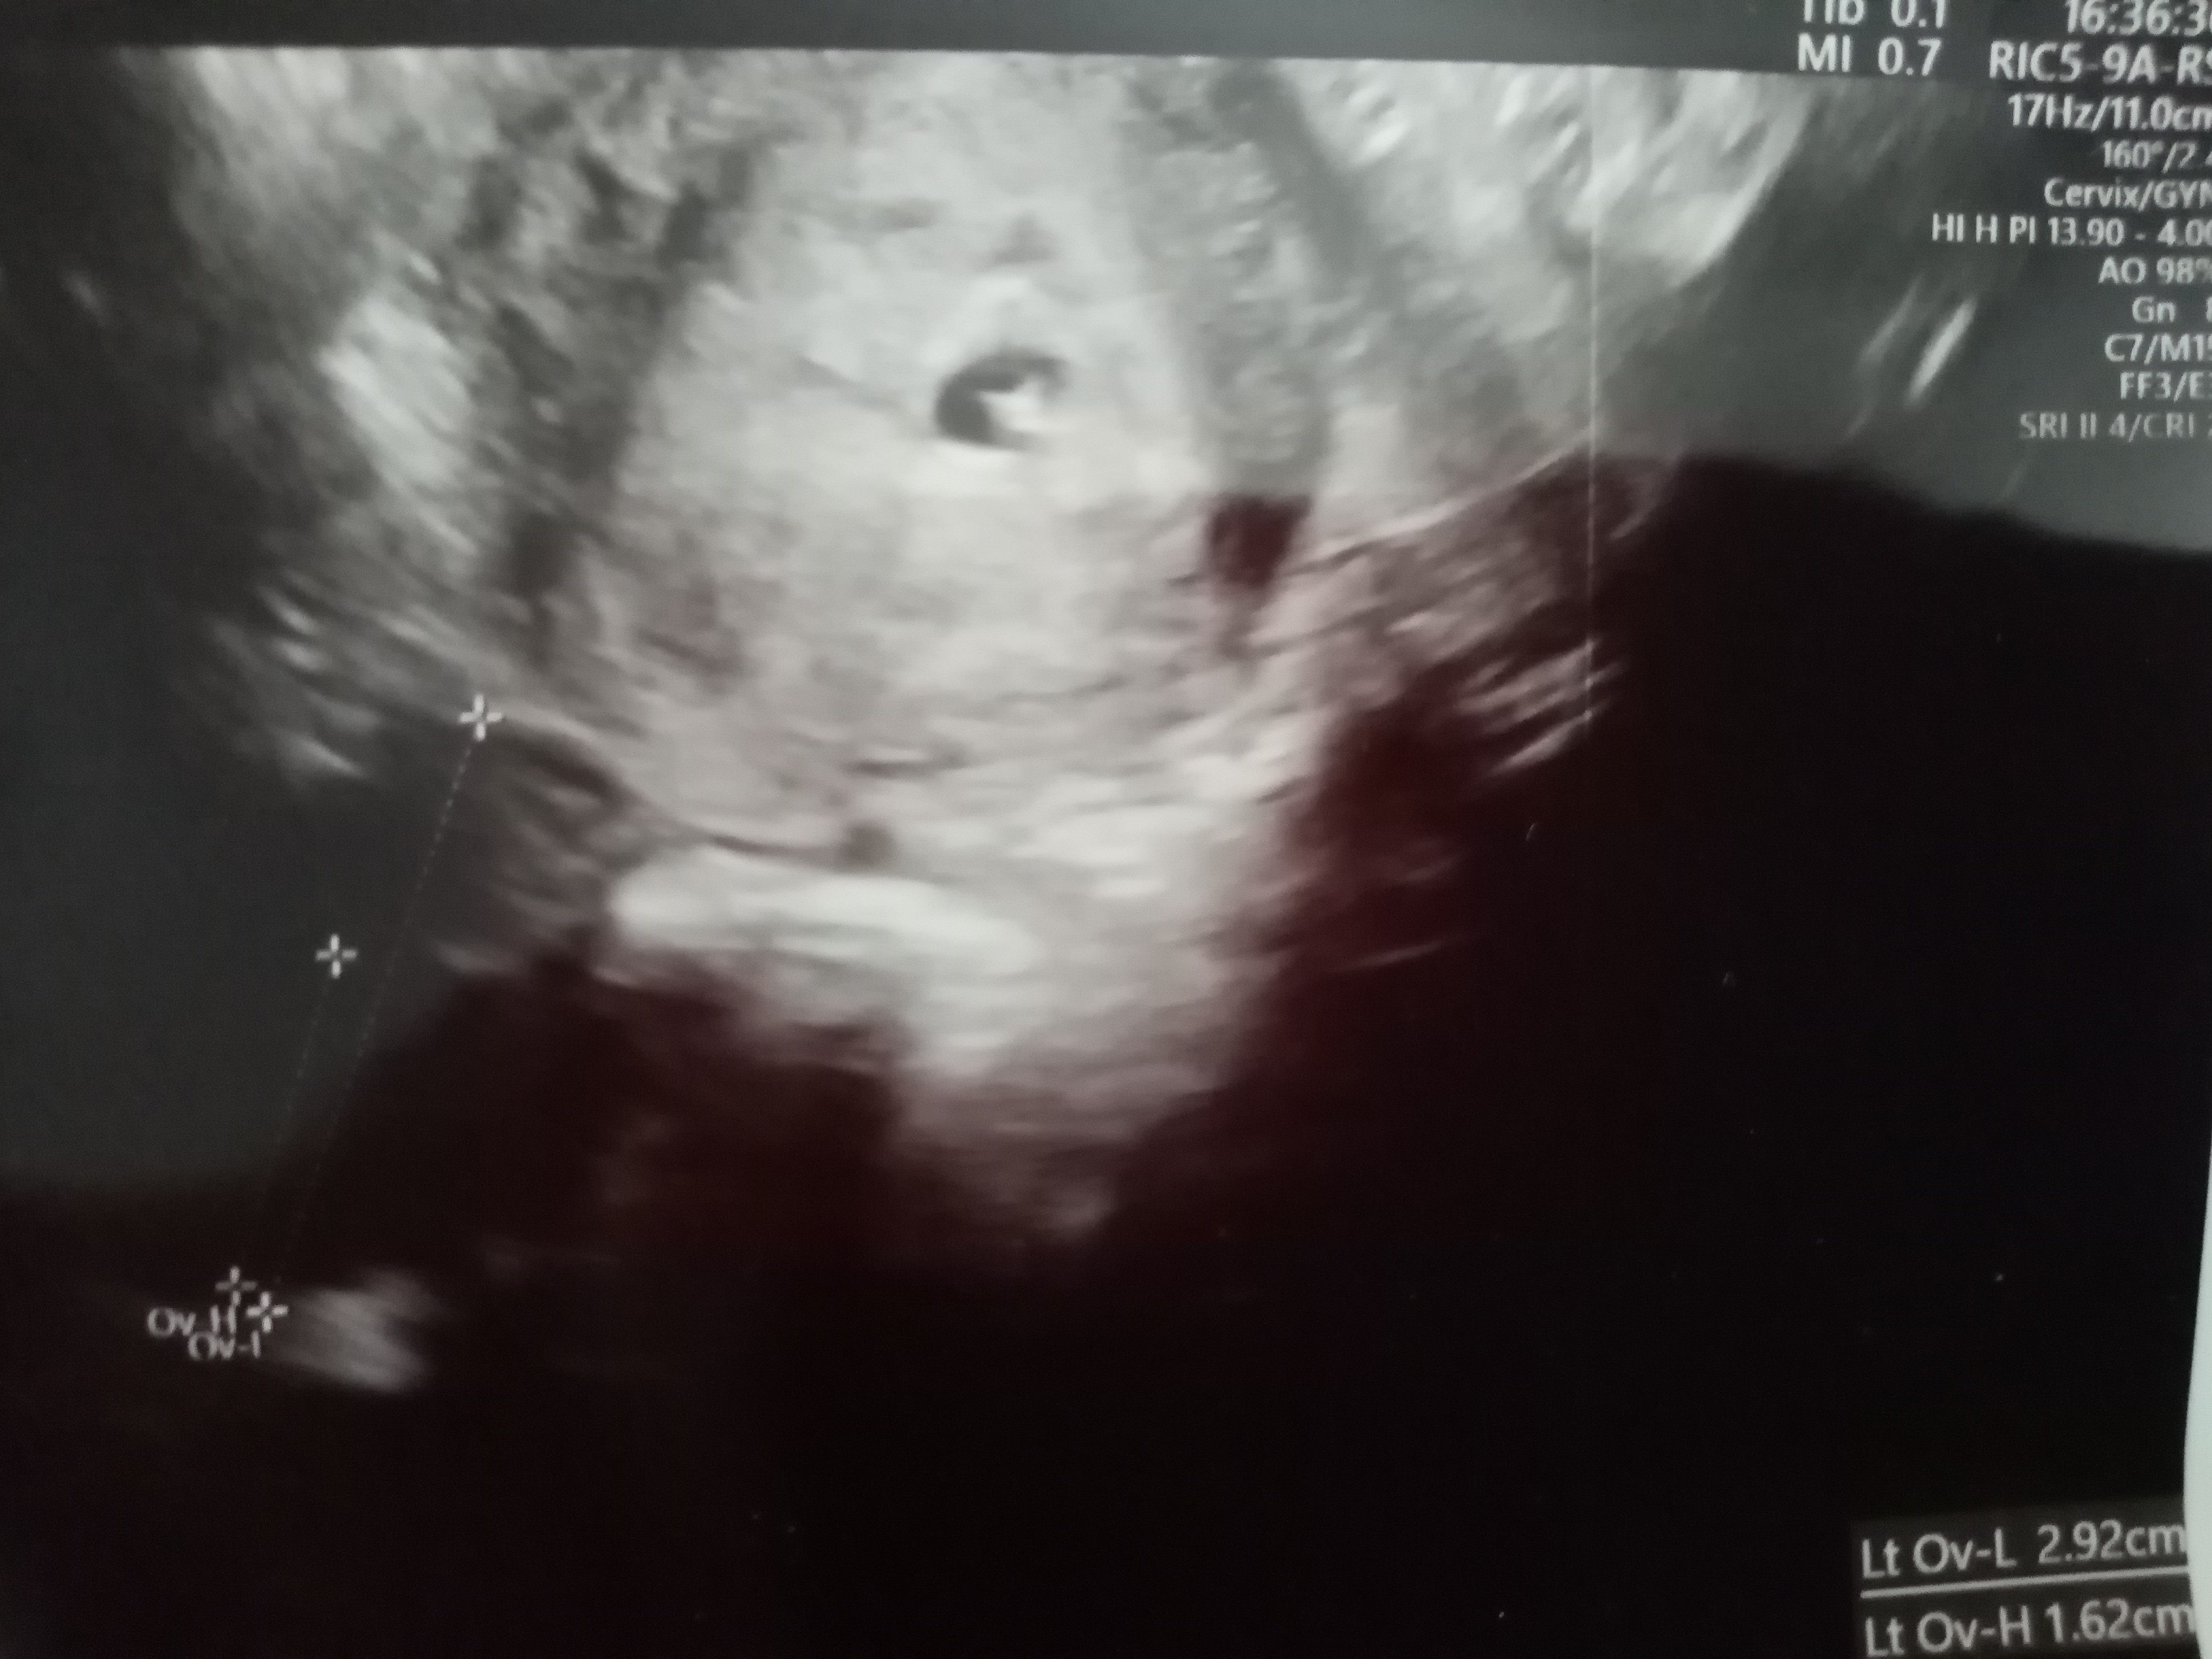

Witam się nieśmiało. Ostatnia OM 8 Mają. Dzisiaj byłam u ginekologa 5t5d i jest narazie tylko pęcherzyk 5mm ale to w środku to może być już zalążek zarodka? Jak myślicie

A lekarz nie mówił czym jest to białe pole w środku pęcherzyka? 🙂 kiedy masz następna wizytę? Opowiedz coś o sobie - ile masz lat? Która to ciąża? ☺

Mówiła że może to być zarodek ale jeszcze bez echa serca. Dwa dni temu pęcherzyk był jeszcze bardzo malutki i bałam się że coś może być nie tak.